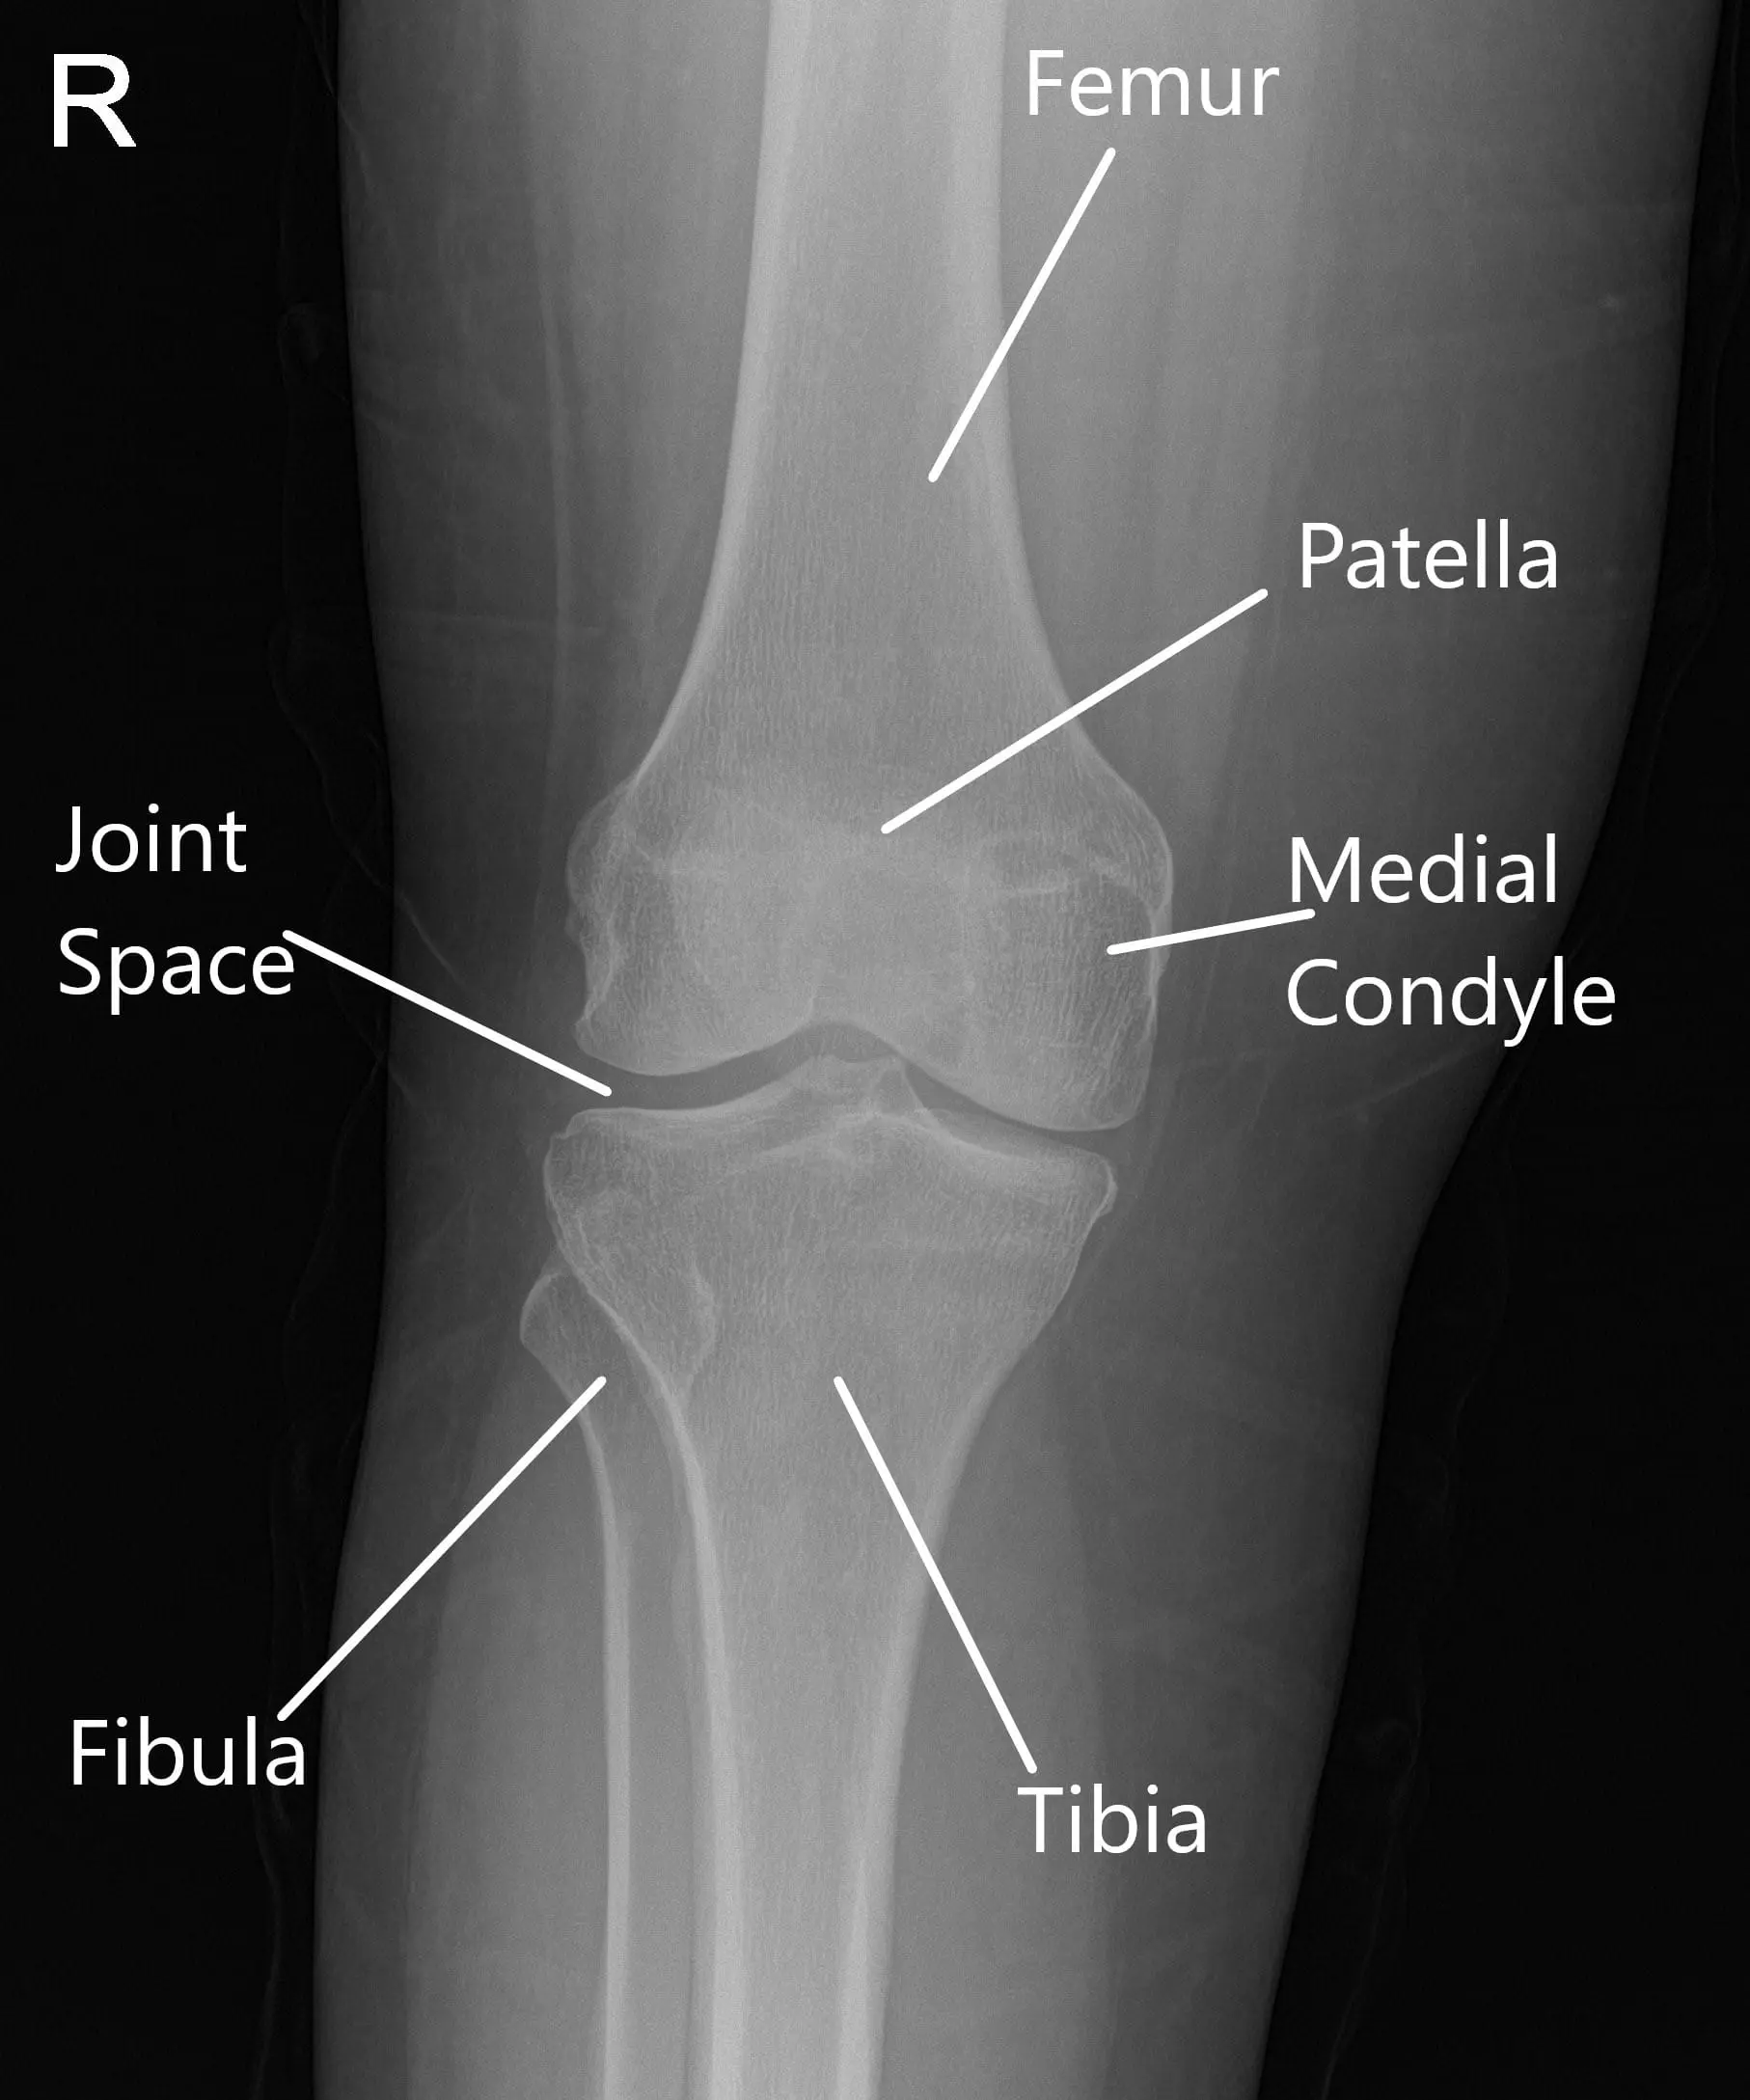

La radiografía de la rodilla derecha indicó osteoartrosis leve en el compartimento medial y anterior de la rodilla.

Se estableció un portal de entrada lateral y se examinó la articulación de la rodilla. Se encontró un desgarro periférico del menisco medial. También se encontró una lesión osteocondral de grado 1 a grado 2 en el cóndilo medial del fémur. El ligamento cruzado anterior presentaba algo de desgaste y degeneración.

No había lesión en el menisco ni en el fémur lateral ni en el cóndilo. Se inspeccionó la articulación patelofemoral y se encontró en buen estado. Ahora se realizó la reparación del menisco medial. Se usaron suturas FasT-Fix. Se utilizaron siete suturas para fijar la rotura periférica desde el cuerno posterior hasta la mitad del cuerpo.